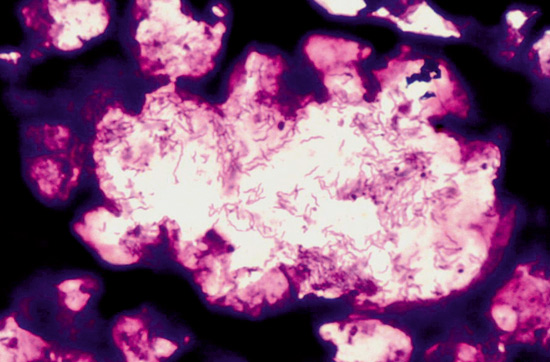

Picture 4.4.3 e (by J. Pohlenz)

Silver staining (W&S) of a colonic section of a pig, infected with Brachyspira hyodysenteria: Cork screw-like black stained bacteria in the lumen of crypts (~500x). Note that Lawsonia intracellularis will also be stained by this method. For clear differentiation use IHC with specific monoclonal antibodies.